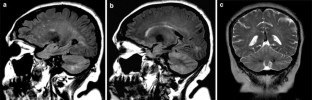

Diffuse cerebellar MR imaging changes in anti-Yo positive paraneoplastic cerebellar degeneration

Fig. 1